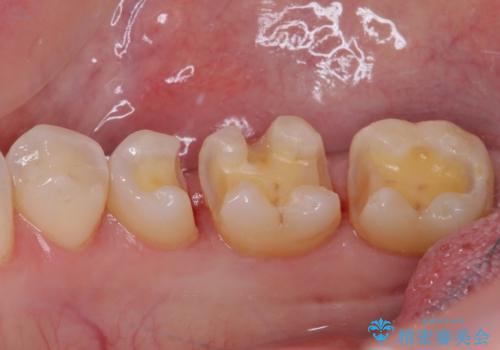

まず麻酔をして銀歯を外し、むし歯を除去し、形を整えて型取りします。

そして次の来院時、セラミックインレーを装着し、噛み合わせなどの調整を行います。

インレーを装着するときは、唾液や血液による接着力の低下を避けるためにラバーダム防湿を行いました。